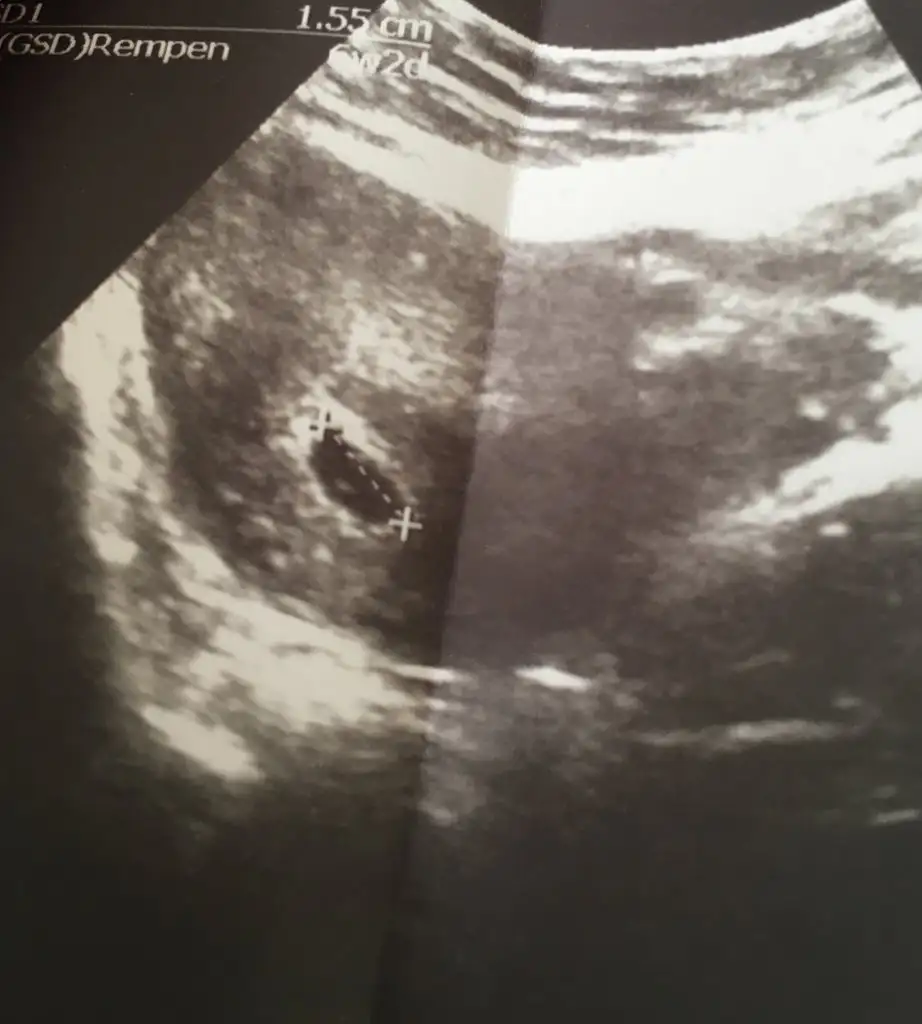

Kızlar bende merak ediyorum 7+5 ken düşük tehlikesiyle gitmiştim monitör ü çektim foto istemedim bide idrarın açık sarıysa erkek oluyormuş duydunuz mu?